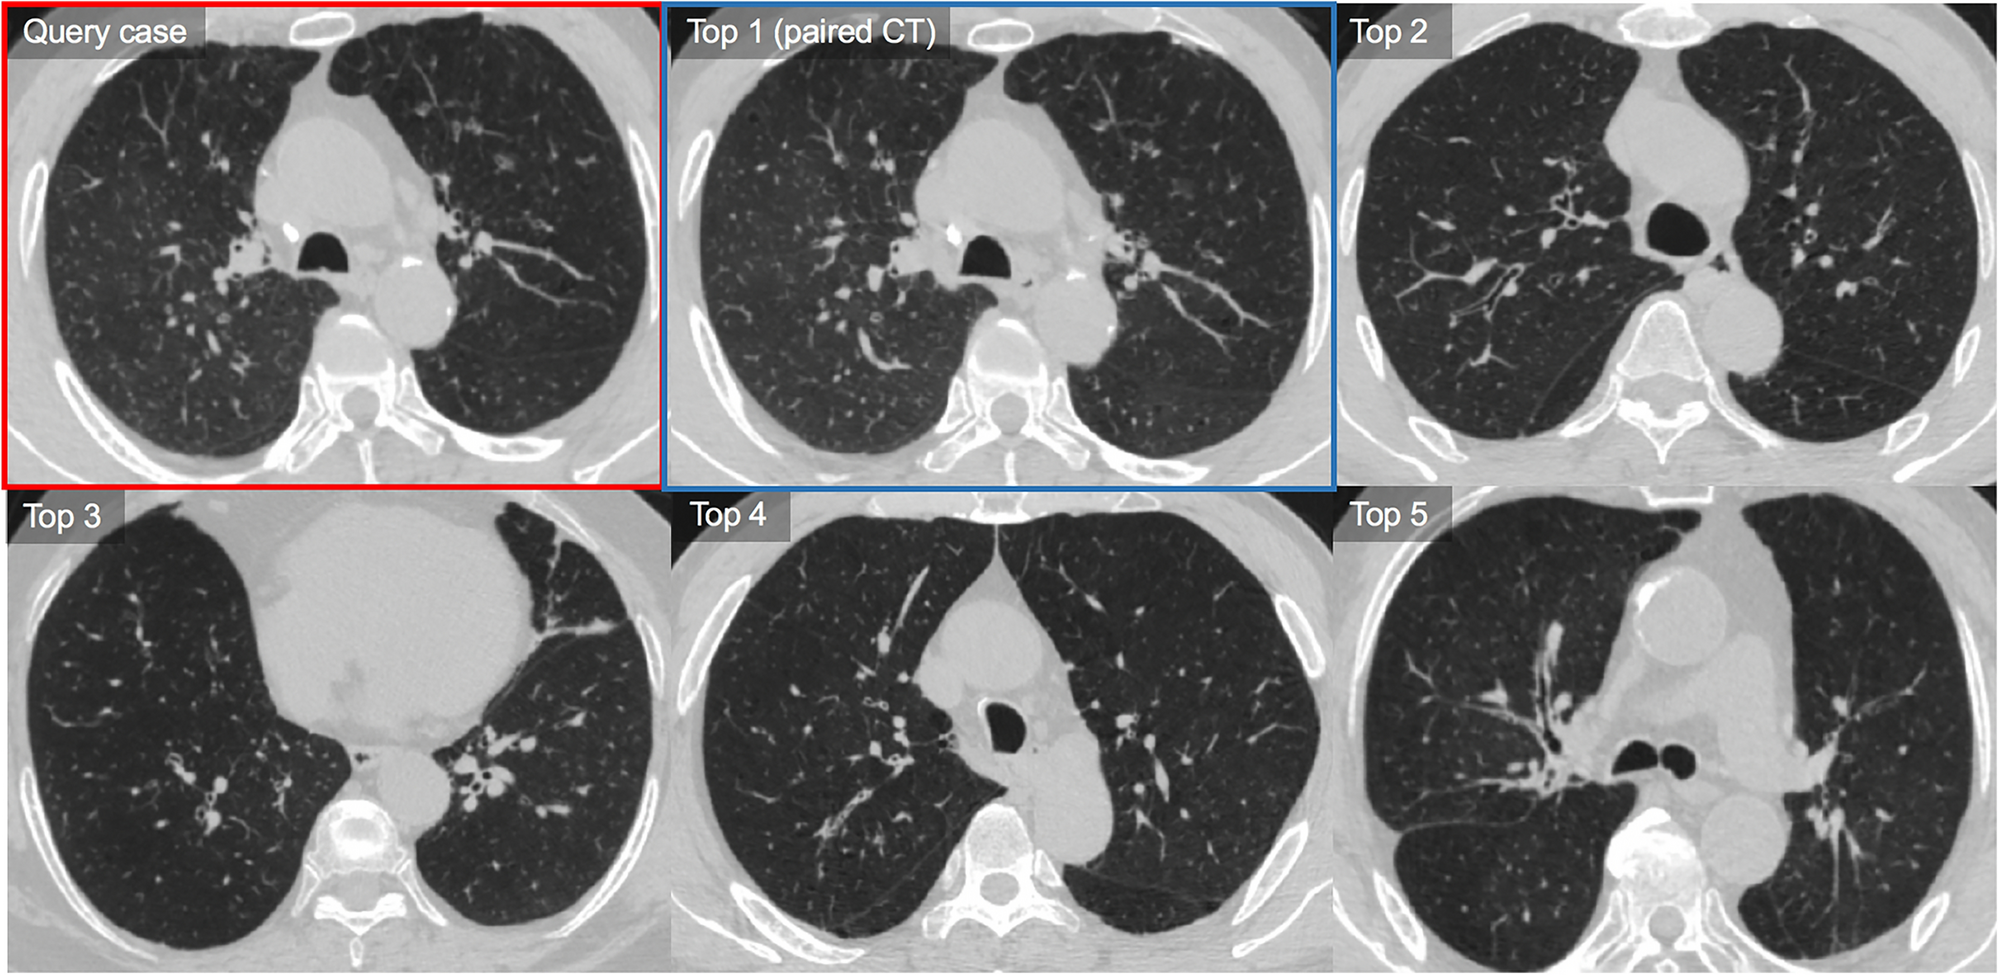

Figure 5

Representative case of the use of the content-based image retrieval (CBIR) system for chronic obstructive pulmonary disease. The query CT shows diffuse bronchial wall thickening in both lungs with multifocal mosaic parenchymal attenuation (Pi10 = 7.1, PVV = 0.55, LAA = 2.9 and D-slope = 3.9). CBIR system retrieves five similar CTs based on the measured similarity in descending order. The query case is outlined with a red box and its paired case (a pair of baseline CT without interval change compared with the query case [follow-up CT]) among the retrievals is outlined with a blue box. Our CBIR system retrieved the baseline pair of query CTs from the database as the top 1 retrieval. CT images of top 2 to top 5 retrievals also show quite similar CT features showing bronchial wall thickening with or without endobronchial mucus plugging and mosaic parenchymal attenuation. No retrieval CT cases demonstrates more than moderate extent of emphysema. In the visual similarity assessment, two chest radiologists rated the similarity scores of the top 1 to 5 as 5, 5, 4, 4, and 4, respectively, and the other chest radiologist as 5, 4, 5, 4, and 4.